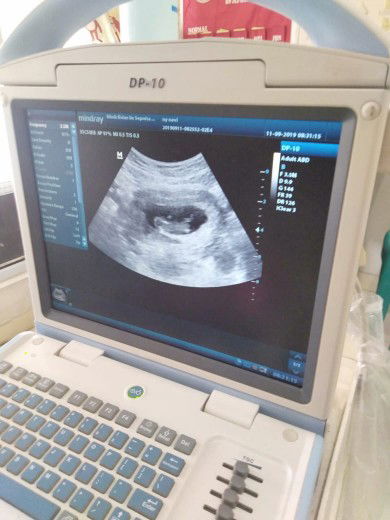

USG

bun mau tanya apakah ada yang sama ky sy, kmrn usg hamil 10w janinnya udh gerak2 kakinya nendang2 gambarnya jelas banget saking jelasnya liat janin nendang2 aku dan suami seneng bnget. sampe dokter nya bilang masya allah pdhl masih kecil ya tapi udh aktf bngt